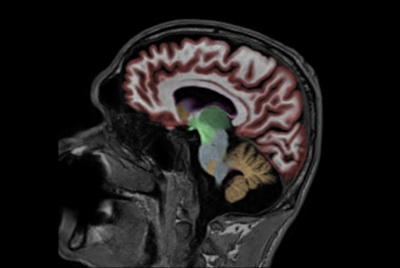

NeuroQuant